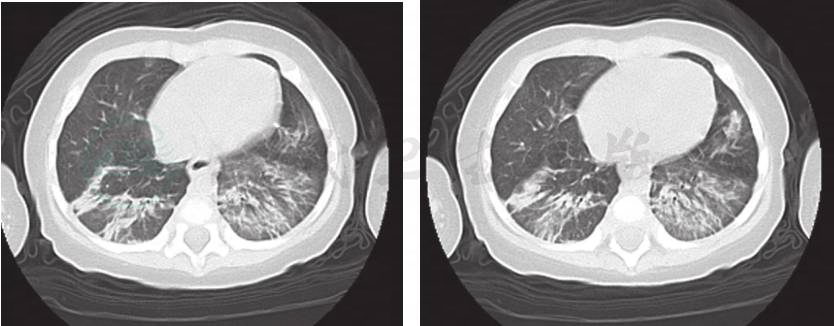

6.肺部CT(图1) 双肺段多发斑片影、结节影,以双肺下叶为著,未见胸腺影。

图1 入院后完善肺CT检查,提示:双肺段多发斑片影、结节影,以双肺下叶显著,未见胸腺影

患儿入院后给予对症治疗:亚胺培南西司他丁钠0.2g,每6小时1次,静滴10天;盐酸万古霉素65mg,6小时1次,静滴 10天;丙种球蛋白2.5g,每天1次,共8天。入院第4天患儿口腔咽后壁及软腭发现黄白脓性物,上软腭与鼻道间形成瘘,鼻腔有血性液体流出,而后转为黄白色脓性液体。鼻腔分泌物培养:铜绿假单胞菌;鼻腔分泌物涂片找到革兰氏阳性菌,腰穿脑脊检查未见异常。入院治疗2天体温平稳,于入院第6天体温再次升高为38.2℃。复查肺CT:双肺下叶渗出性病变较前吸收,双肺上叶出现结节状影,边缘有毛刺征。检测1,3-β-D葡聚糖1.33mmol/L,考虑合并真菌感染。予抗真菌治疗:伏立康唑40mg,每12小时1次,静脉滴注1天后改25mg,每12小时,共静脉滴注12天;第2天体温降37.2℃左右。住院治疗18天,复查血细菌培养阴性,复查肺CT:双肺炎症较前进一步吸收。于上海交通大学医学院附属新华医院行基因分析结果为T-B+SCID,受体γ链(γc)基因缺陷,X连锁的IL-2Rγ链缺陷。患儿母亲为携带者。故确诊为SCID。家长因经济原因最终放弃治疗。